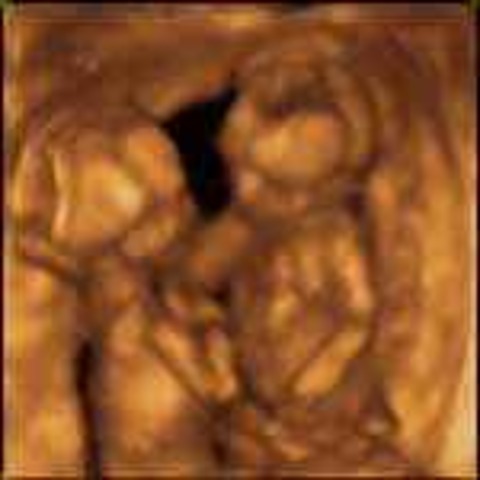

• Week 25

Week 25

.•The unborn child is 34 cm in length and weighs almost 690 grams.

•Baby is around 13.5 inches in length and weighs 1 and half pounds.

•Bones are becoming solid, hands are now fully developed.

•The brain is growing rapidly, the brain cells are starting to mature.

•The sexual organs are fully developed.